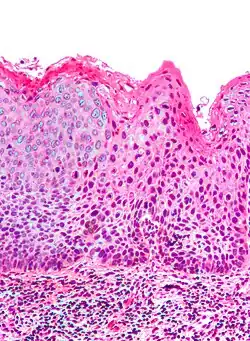

Micrograph of (classic) vulvar intraepithelial neoplasia III. H&E stain. | |

-

Micrograph of vulvar intraepithelial neoplasia III. H&E stain.